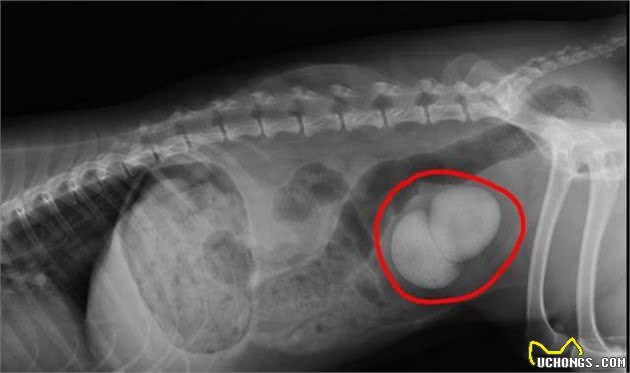

在狗的尿液中,结石通常是由于盐的沉积而形成的。一般来说,尿路结石的体积不是很大,数量也不是很大。尿路结石的形态多为菱形或三角形,可对尿道产生极大、完全或不完全的刺激,引起犬的尿路闭锁和肾性腹痛症状。至于狗呢也会出现拱背缩腹、常呈排尿姿势等表现。

如果结石很大,仅仅用药治疗是不好的,最好是或是到医院开展手术治疗,要不然结石长期不取下,狗狗排尿不出,就会发生身亡的状况,因此,一定得开展立即医治。